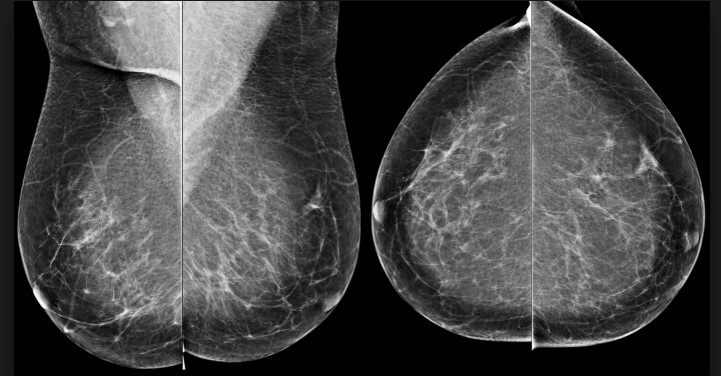

Pandangan Mamografi

Ini melibatkan pengambilan rontgen payudara dalam 2 tampilan setiap tahun atau dua tahun sekali mengikuti pedoman yang direkomendasikan.

- Tampilan MLO (medial lateral oblique view)

- Tampilan CC (cranial-caudal view)

MMG – pandangan MLO MMG – pandangan CC

MMG – pandangan CC MMG –pandangan MLO